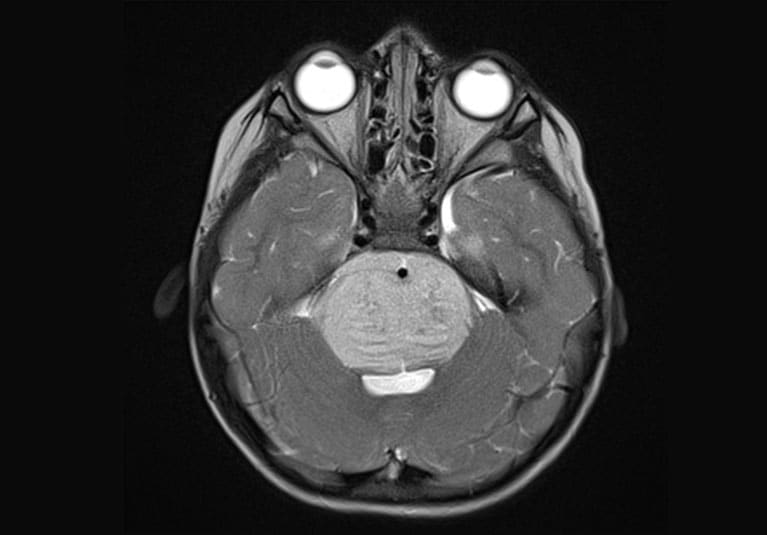

Axial T2-weighted MRI scan with contrast

Axial T2-weighted MRI scan with contrast demonstrates the typical appearance of a newly diagnosed diffuse midline glioma. The patient presented with new-onset ataxia and underwent a biopsy, which confirmed the presence of an H3KM-mutated glioma. The patient received fractionated radiation therapy.